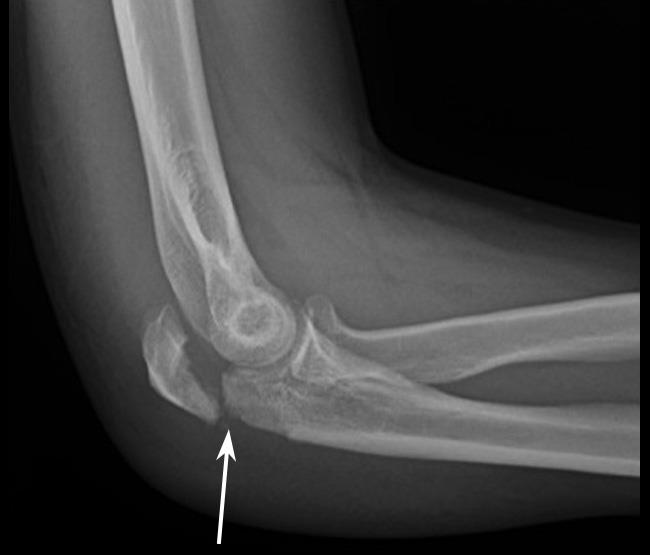

Golfers Elbow

Similarly to tennis elbow, golfers elbow (or medial epicondylitis) is a tendon overload injury associated with the wrist flexors located in the forearm. The wrist flexors attach to the bony prominence located on the inside of the elbow, and repetitive movements / tasks using this muscle group in excess of its current capacity results in an acute reactive change in the tissue.